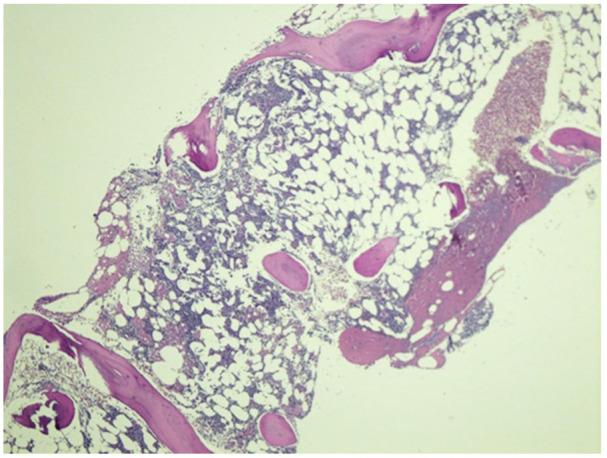

Pure red cell aplasia (PRCA) is a rare disorder mainly affecting the erythroid precursor cells. It presents with severe isolated reticulocytopenia with relatively normal counts in the myeloid and megakaryocytic lineages. It has been attributed to numerous congenital and acquired causes. DNA Methyl Transferase 3 Alpha (DNMT3A) mutation has been typically associated with myeloid and lymphoid malignancies. There is a scarcity of data regarding the association of DNMT3A mutation with PRCA. We report a case of a 73-year-old man who initially presented with anemia and reticulocytopenia. After a thorough evaluation and eventual bone marrow biopsy, he was diagnosed with PRCA. Further genetic testing identified a DNMT3A mutation. We are reporting this rare case to highlight the fact that DNMT3A mutation can also present as isolated PRCA in and of itself without the co-occurrence of leukemia, lymphoma, or myelodysplastic syndrome (MDS).

纯红细胞再生障碍性贫血(PRCA)是一种罕见的疾病,主要影响红系前体细胞。它表现为严重的孤立性网织红细胞减少,而骨髓和巨核细胞谱系的计数相对正常。它已经归因于许多先天性和后天性的原因。DNA 甲基转移酶 3A(DNMT3A)突变通常与髓系和淋巴恶性肿瘤有关。关于 DNMT3A 突变与 PRCA 的关联的数据很少。我们报告了一例 73 岁男性的病例,他最初表现为贫血和网织红细胞减少。经过彻底的评估和最终的骨髓活检,他被诊断为 PRCA。进一步的基因检测发现了一个 DNMT3A 突变。我们报告这个罕见的病例,以强调一个事实,即 DNMT3A 突变也可以单独表现为孤立性 PRCA,而不伴有白血病、淋巴瘤或骨髓增生异常综合征(MDS)。